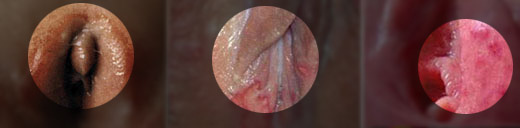

(2)女性典型症状:阴道炎和尿道炎:白带增多、脓性;有腰痛、下腹痛;子宫颈红肿、触痛;宫颈口糜烂;部分可有较轻的尿频、尿急、尿痛,尿道口红肿及少量脓性分泌物。